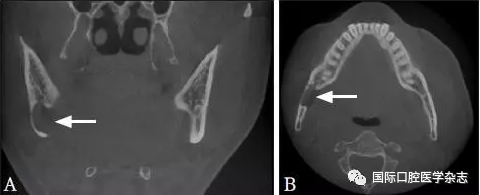

Stafne骨腔又稱下頜舌側(cè)骨缺損或下頜骨發(fā)育缺損,由Stafne在1942年首次報(bào)道,通常是拍片偶然發(fā)現(xiàn),大多認(rèn)為是下頜骨舌側(cè)皮質(zhì)骨受頜下腺壓迫所致。X線片典型表現(xiàn):與牙無關(guān)的透射影,通常位于下頜神經(jīng)管下方,第一磨牙與下頜角之間的部位(圖10)。當(dāng)其發(fā)生在下頜骨前份且與牙根接觸緊密時(shí)可能混淆診斷[32-33]。通過CBCT顯示下頜骨舌側(cè)骨質(zhì)缺損結(jié)合磁共振成像比較病變組織與唾液腺的信號(hào)強(qiáng)度進(jìn)行診斷,可避免不必要的手術(shù),一般認(rèn)為不需要干預(yù)。

A:冠狀位;B:水平位。

圖 10 Stafne骨腔的CBCT圖像

Fig 10 CBCT of Stafne’ bonecavity